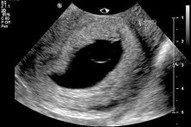

Copy from dr emelda Inilah ultrasound scan rahim ibu yang sudah hamil hampir 3 bulan. Di dalam rahimnya ada kantung kehamilan yang mengandungi air ketuban (air akan kelihatan hitam melalui imbasan ultrasound scan), tetapi tiada janin yang terbentuk di dalam kantungnya. Dari permulaan kehamilan lagi memang tidak ada janin. Inilah yang dinamakan kehamilan tanpa embryo, atau anembryonic pregnancy. 40% wanita yang mengalami keguguran ada kehamilan tanpa embryo. Ada ramai juga yang walaupun ada pembentukan janin, tetapi janin itu tidak normal dan gugur. Sebabnya ialah terdapat kerosakan baka DNA kepada benih telur atau sperma, yang apabila dipersenyawakan tidak boleh menjadi. Walaupun kita manusia yang sihat, bukan semua benih kita sempurna. Tetapi, banyak kes sebegini, keguguran tidak selalunya berlaku dengan serta-merta, sebab itulah bila kita buat ultrasound scan 8 minggu sehingga 12 minggu kehamilan, kantungnya sudah besar tetapi kosong, dan keguguran masih belum berlaku. Pada hakikatnya, untuk kehamilan yang sihat, kita sudah boleh melihat janin terbentuk melalui ultrasound scan sejak 5-6 minggu kehamilan lagi dan boleh lihat denyutan nadi jantung janin. Sudah terlalu banyak kali, saya jumpa kes sebegini bila ibu-ibu hamil datang ke klinik berjumpa dengan saya. Kebanyakannya akan mengalami keguguran dengan sendirinya sebelum 3 bulan. Mereka datang ke klinik untuk ultrasound scan kerana sudah mula melihat sedikit pendarahan menandakan proses keguguran sudah bermula. Mereka tanya saya, adakah sebabnya mereka makan buah nenas semalam, adakah sebabnya mereka minum air kelapa minggu lepas, adakah sebabnya mereka minum air tebu bulan lepas. Adakah sebabnya mereka angkat benda berat pagi ini. Adakah rahim tidak kuat. Jawapan saya ialah TIDAK, Puan. Puan tidak bersalah. Tiada makanan yang menyebabkan masalah ini, dan kegiatan fizikal anda tidak menyebabkan masalah ini. Ini bukan sebab rahim tidak kuat. Sebab itulah saya kata, jangan salahkan diri sendiri. Sebab itulah saya berkata kepada semua orang lain, jangan mencari kesalahan wanita yang mengalami keguguran. Jangan buat fitnah kepada buah nenas. Pada hakikatnya, sudah memang pun kehamilan itu tidak boleh menjadi, sebelum ibu itu makan buah nenas lagi. Credit :DrEmelda Banyak penjelasan yang saya sudah sampaikan dalam program #TanyaDrImelda Episod 3, tentang keguguran dan kenapa ia berlaku.